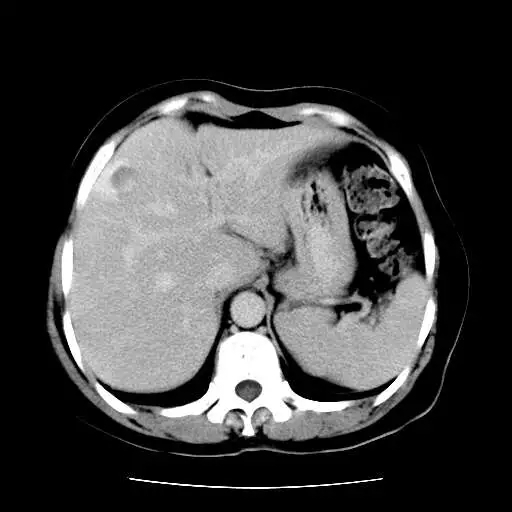

继续接上个病例经手术病理证实的肝海绵状血管瘤,CT平扫加增强共5期,表现相当典型。女性, 52;上腹疼痛半年.彩超示:肝内强回声团,考虑血管瘤.